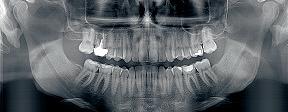

pantomogramach. Aparat generuje jasne i ostre

obrazy cyfrowe

Możliwości panoramy CS 8100

![]() Panoramy segmentowe ze zredukowaną dawką |